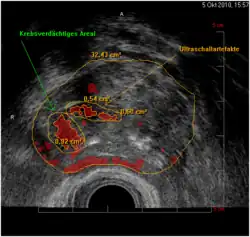

HistoScanning-Befund: rot markiert die krebsverdächtigen Areale, auf der rechten Seite der Prostata gelegen

Bei Ultraschallbildgebungsverfahren werden die gewonnenen Ultraschalldaten umgesetzt in Grautöne, um so ein Bild zu erzeugen und vorhandene Strukturen zu visualisieren. HistoScanning ist kein Ultraschallbildgebungsverfahren, sondern Ultraschall wird lediglich quasi als „Werkzeug“ eingesetzt. Idee der Entwickler war, eine KI auf die Erkennung von Prostatakrebs zu trainieren, indem man sie mit Sonografiedaten und dazu korrespondierenden Gewebeschnitten füttert. Der Trainingsdatensatz bestand aus den Daten von 14 Patienten, deren Prostata operativ entfernt und vollständig histologisch aufgearbeitet worden war. Der Schallkopf liegt im Enddarm und scannt die Prostata vollständig ab. Drei Algorithmen berechnen Zelldichte, Heterogenität, und Vaskularisierung, und überlagern diese Parameter dem Ultraschallbild farbig.

Diese Gewebedifferenzierung soll dem Anwender eine visuelle Entscheidungshilfe sowohl bei dem Befund wie auch zur Planung einer möglichen nötigen Behandlung bieten. Ob es sich bei den markierten Arealen tatsächlich um Tumorgewebe handelt, kann nur eine anschließende Biopsie feststellen.